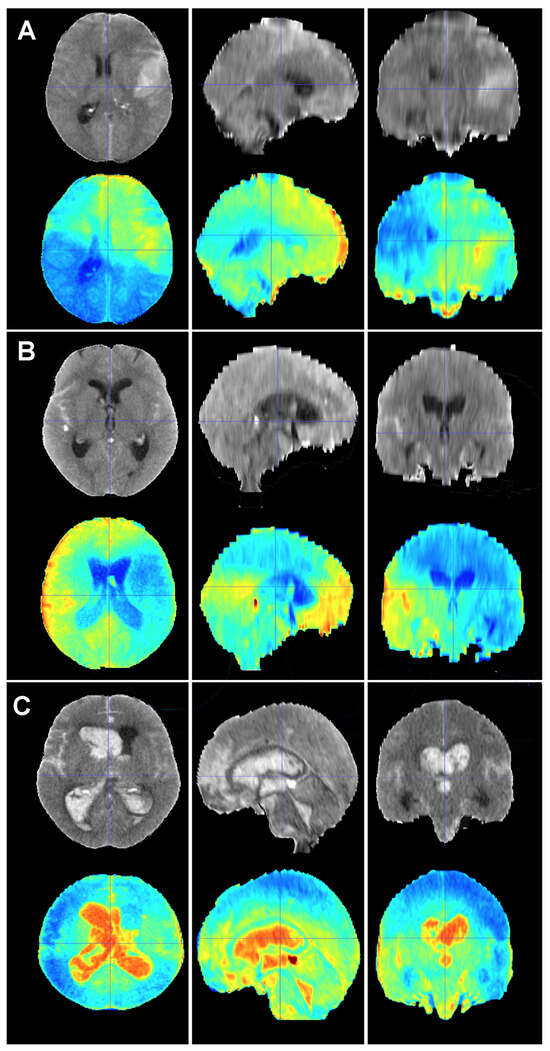

Figure 5.

Baseline CT scan (upper row) and gradient-weighted class activation mapping or Grad-CAM (lower row) for three patients (A–C) from the test cohort who were alive three months after suffering a subarachnoid hemorrhage. Saliency maps highlighted regions in red that were more significant when classifying patients; in this case, into the group of patients who survived the event. Thus, it was possible to create a visual depiction of the process the model followed to allocate patients into each class. These maps highlighted supratentorial brain areas and seemed to disregard hemorrhages, except when they followed a perimesencephalic pattern. (A) A 60-year-old male who suffered a perimesencephalic SAH whose angio-MR and angiography were negative. (B) A 43-year-old male who was diagnosed with a SAH caused by a right middle cerebral artery aneurysm. He was admitted in good condition (WFNS 1) and was surgically treated and discharged without major neurological deficits on postoperative day 19. (C) A 75-year-old female who suffered a SAH and was admitted to the hospital with a WFNS grade 4. The left posteroinferior cerebellar artery aneurysm was coiled. The patient survived the event, but was still severely impaired at the three-month follow-up (modified Rankin Scale: 4).